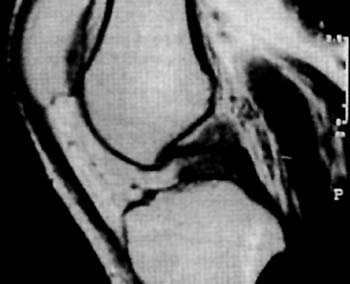

Los estudios Rx, y de TAC fueron en todos los casos negativos, en cambio, se destaca la RNM como metodo fundamental para su diagnostico. (Fig 1)

El mismo se caracteriza por su ubicacion central adosado al Ligamento Cruzado Posterior desplazando hacia lateral al Ligamento Cruzado Anterior.

Su densidad lo asemeja como un tumor con caracteristicas liquidas y su forma multilobulada ocupa practicamente el intercondilo femoral (Fig 2-3-4) En T2 es facilmente distinguible como una masa homogenea que ocupa todo el contorno del condilo femoral interno.

Figura 3